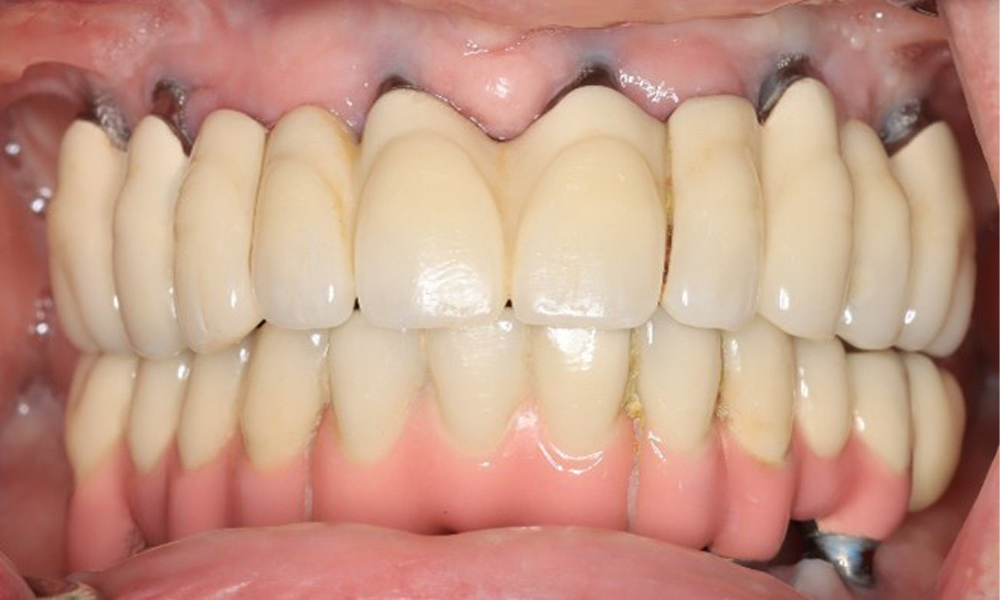

Eine 74-jährige Patientin stellt sich in der Sprechstunde vor. Die Anamnese zeigt, dass die Patientin gut eingestellten Bluthochdruck hat und Lixiana einnimmt. Weiterhin hatte die Patientin im Jahr 2020 ein Nierenkarzinom. Die Lebensgewohnheiten der Patientin sind unauffällig. Die Patientin hat keine eigenen Zähne mehr. Sie hat im Oberkiefer und Unterkiefer jeweils sechs Implantate, die mit Kronen bzw. über Brücken versorgt sind. Anhand der aktuellen Befunde lässt sich keine periimplantäre Mukositis bzw. Periimplantitis feststellen; vereinzelte (geringfügige) Blutungen an den Implantat(-versorgungen) liegen vor.

Die periimplantäre Situation ist derzeit stabil. Aufgrund der Komplexität der Suprakonstruktionen hat die Patientin ein moderates Entstehungsrisiko und ein geringes Progressionsrisiko für periimplantäre Erkrankungen.